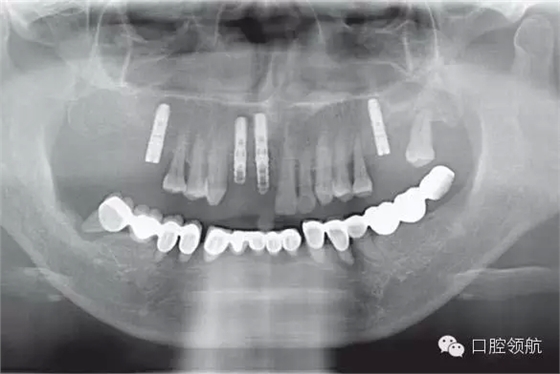

下頜為十?dāng)?shù)年前制作的三組金屬烤瓷橋修復(fù)體。右下4、5、7帶缺失的6;右下3、1及左下1、2帶缺失的右下2;左下3、4、5、8帶缺失的6、7,左下8修復(fù)后牙齒自然脫落,全景片無左下8的影像。幾乎所有的余留牙周圍的骨質(zhì)均吸收到根尖1/3。臨床上三組下頜金屬烤瓷橋均有較大幅度的松動(圖6-7,圖6-8)。

圖6-8 下頜術(shù)前全景片